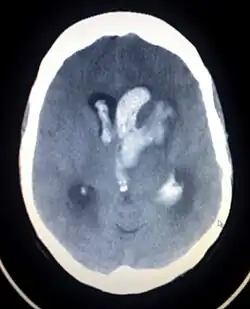

| Recent hemorrhagic infarcts. | |

Otherwise known as hemorrhagic stroke, these account for approximately 15% of all strokes.[5] Classified according to one of four origination sites, intracerebral (ICH), subarachnoid, subdural, or epidural. Both subdural and epidural hemorrhages are most always caused by trauma, therefore, they are not considered hemorrhagic strokes.[5]

- Hypertension is the predominant cause of intracerebral hemorrhage. The clinical presentation and signs and symptoms depend on the location of affected structures in the brain and which vessel is involved. A non-contrast Cat Scan of the head should be utilized as the primary imaging modality during initial diagnosis. Prognosis and treatment are determined by location and size of the hemorrhage.[5]